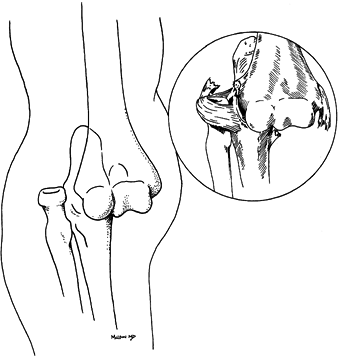

ligaments (Fig. 16.21). Usually, this strong

musculoligamentous complex binds the radius and ulna securely, so that

both bones dislocate together in a linear fashion. Therefore, isolated

dislocation of either bone is uncommon, although dislocation of the

radial head is frequently associated with fractures of the proximal ulna (139) (i.e., Monteggia type 1 injury) (Fig. 16.22).

In children, the ulnar fracture can be subtle, consisting only of mild

ulnar bowing in association with a dislocation of the radial head,

![]() |

Figure 16.21. Divergent dislocation of the elbow.

Figure 16.22. Anterior dislocation of the radial head. The radius and capitellum are not colinear.